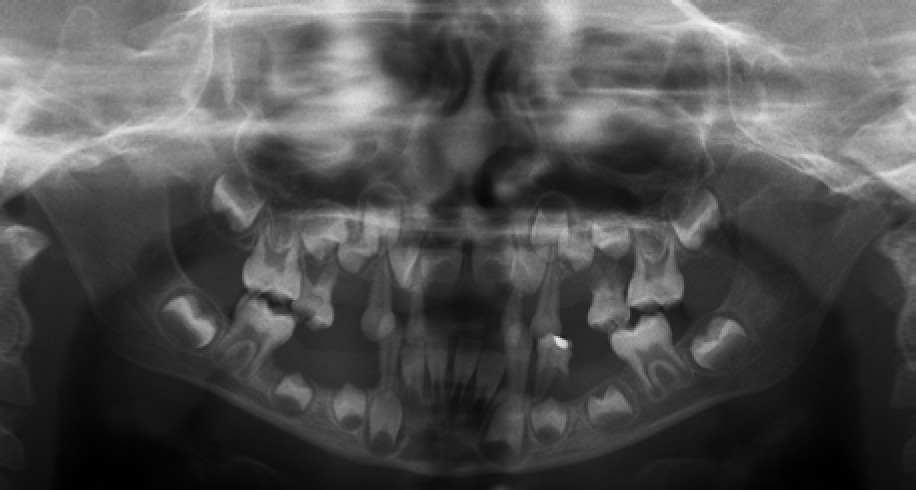

When he was 5 years of age the intraoral examination revealed incomplete primary dentition with five missing teeth, marginal gingivitis, interdental papilla hypertrophy, carious lesions in seven primary teeth, and one permanent tooth of various degrees of advancement for conservative treatment (Fig. 1). The patient was qualified for simultaneous dental treatment under general anesthesia. A panoramic radiograph picture was taken showing the advanced destruction of the alveolar bone in the maxilla and the alveolar part of the mandible. Three primary teeth were completely devoid of bone base. The roots of the lower incisors were only half of their normal length (Fig. 2). Under antibiotic protection (amoxicillin with clavulanic acid at a dose of 30 mg/kg), professional removal of dental plaque and conservative treatment of teeth extraction of four primary teeth with complicated caries and periodontitis were performed. The patient was provided with permanent dental care.

When the patient was 10, the exposure of two-thirds of palatal roots and third-degree loosening of teeth were observed (Fig. 3). A panoramic radiograph picture was taken (Fig. 4), which revealed complete absence of the bone base in all permanent first molars. Teeth 16 and 26 were qualified for extraction, which was performed in an outpatient setting under local anesthesia and antibiotic treatment (clindamycin, 10 mg/kg/dose). The obtained material from granulomatous lesions was submitted for histopathological examination, the results of which indicated non-specific inflammatory granulation tissue.